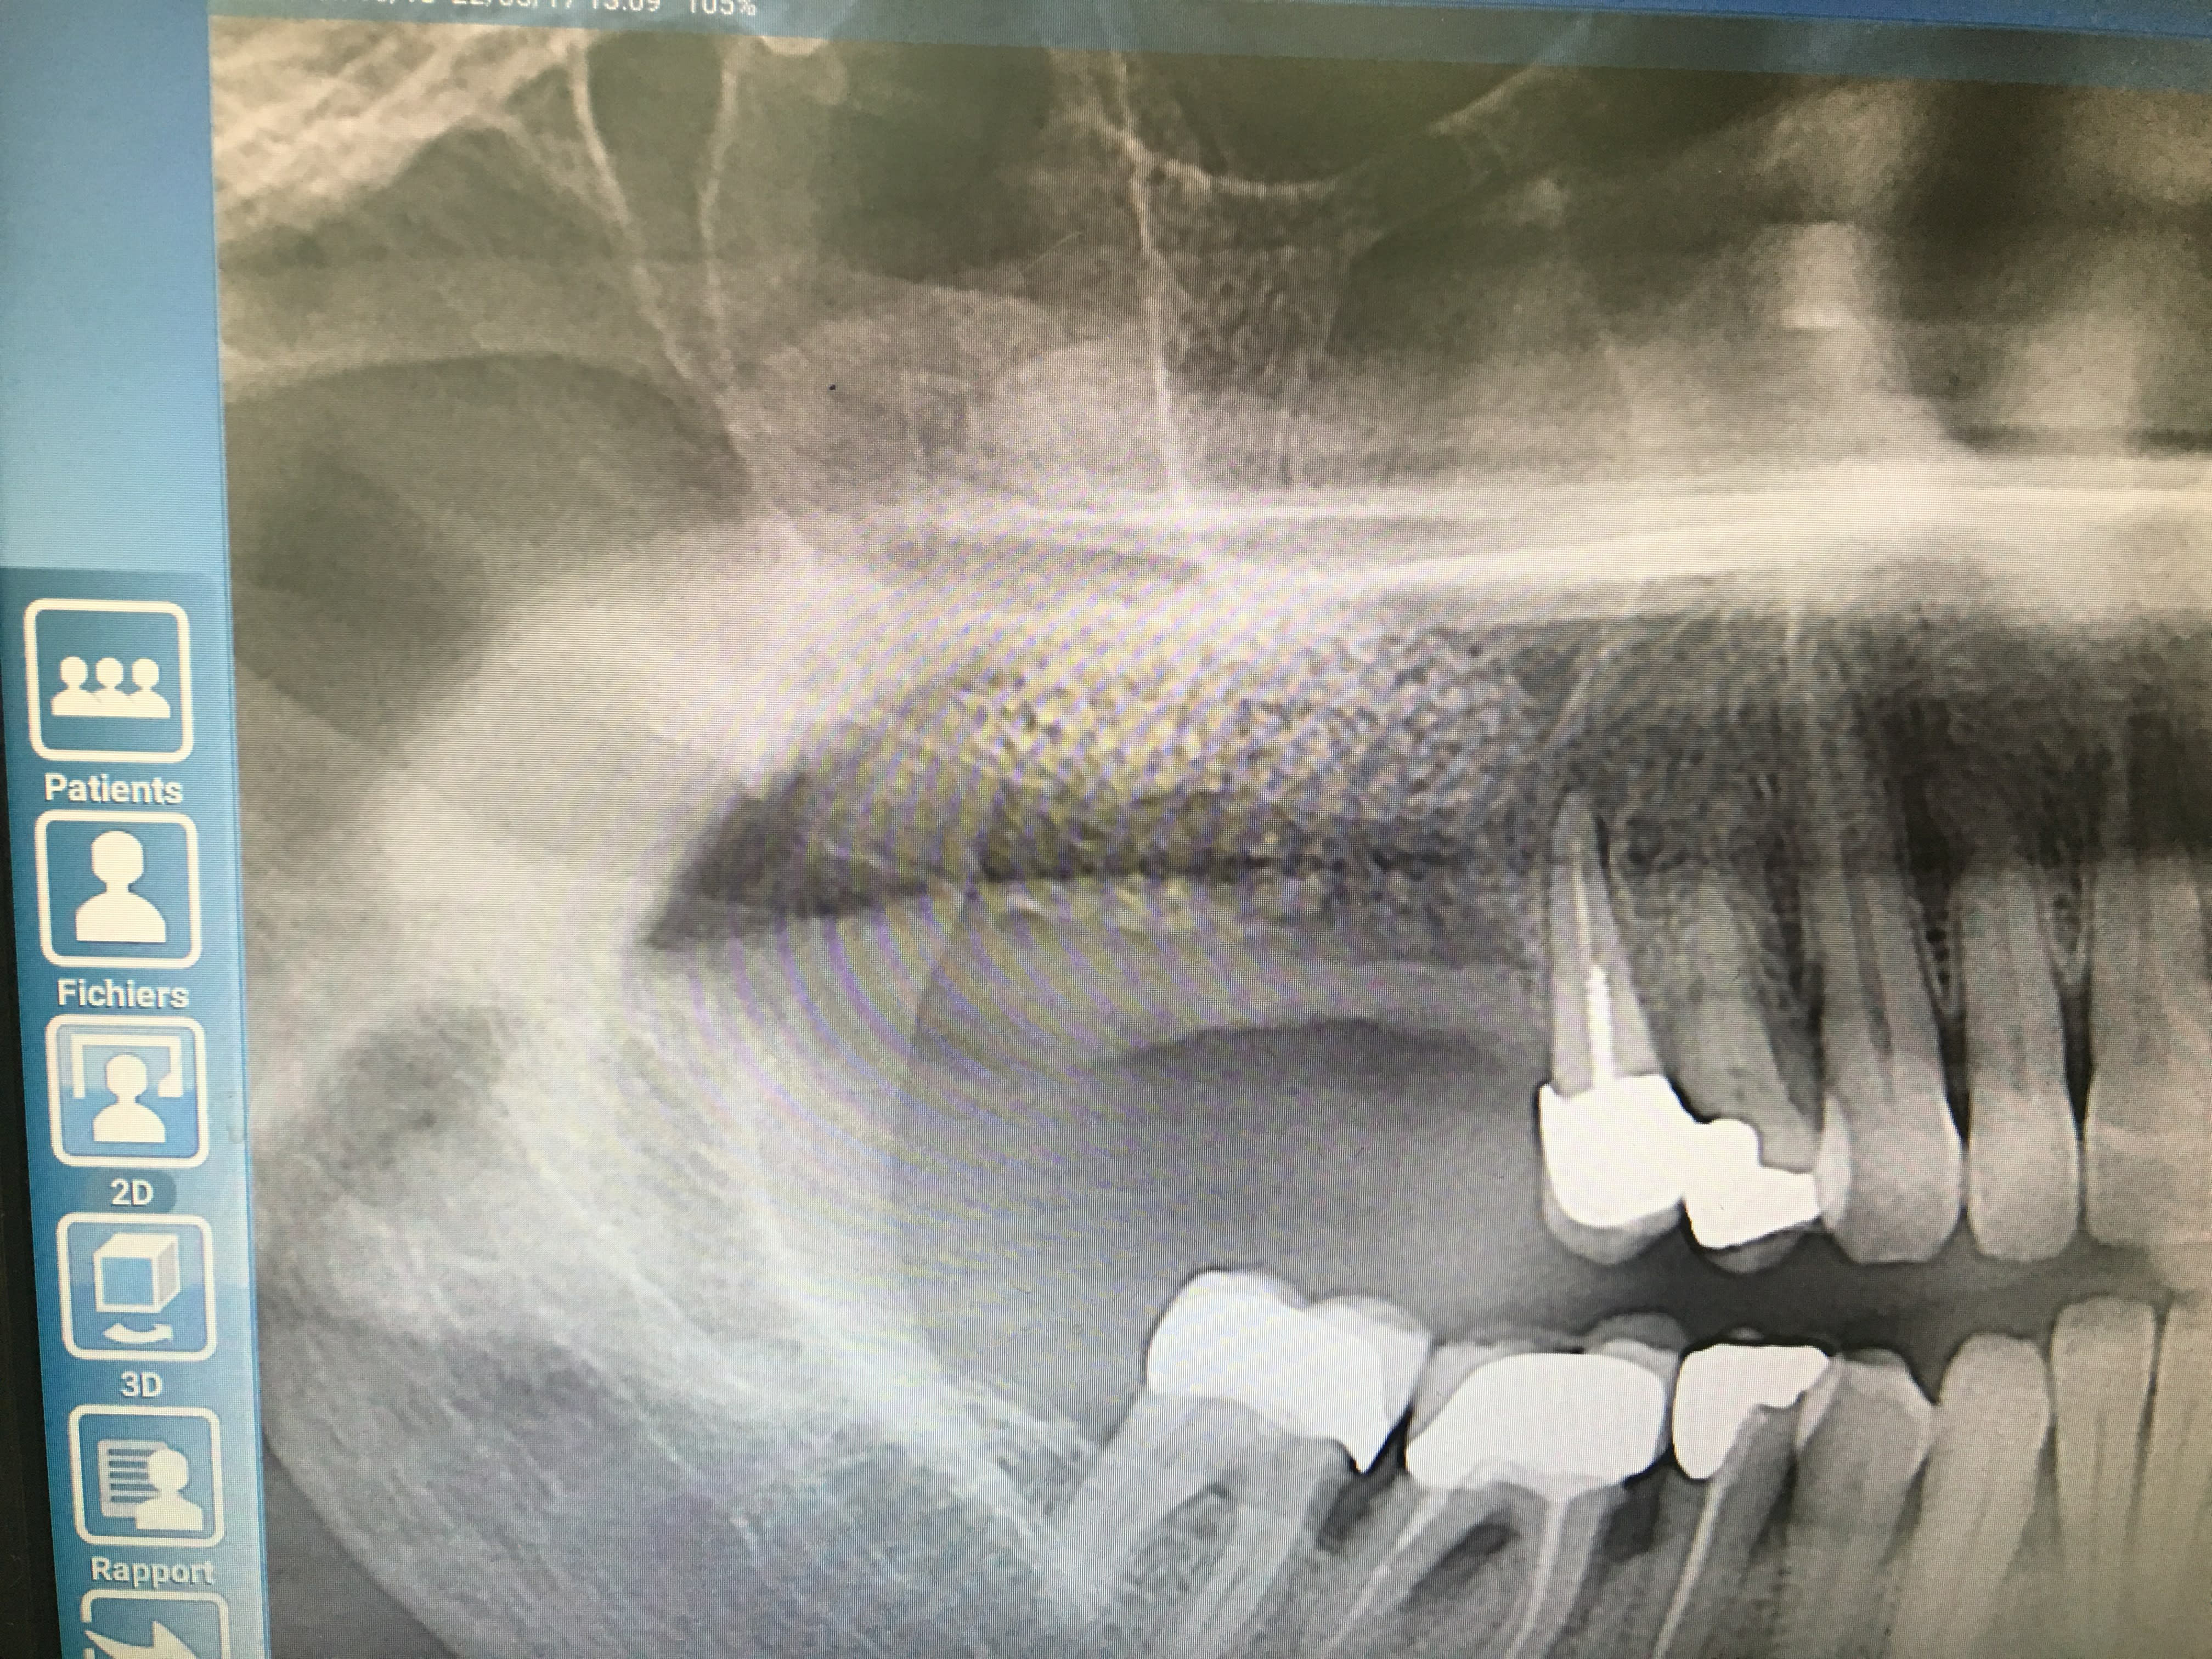

Aie aie aie il va falloir investir dans un cone-beam pour les contrôles post OP, la pano bof bof.

Je fait des panos pour des raisons de ALARA meme si avec les conebeams aujourdui le dose est reduit. (BTW, les images sont des photos d'un ecran donc pas super qualité). Par contre si les autres ont l'habitudes to fair des scans de control, je les suivre.

Non, ca ne m'inquieterais pas, parfois la membrane ne bouge pas (plus epaisse, patient ne respire pas fort, pas le bon jour...), a ce moment j'essaie de verifier son integrite visuellement. En tout cas vu la radio du premier cas aucune inquietude, on voit bien un volume defini, c'est donc qu'il n'y a pas de dechirure. Sur la deuxieme, la qualite est trop mauvaise, franchement je ne vois rien.